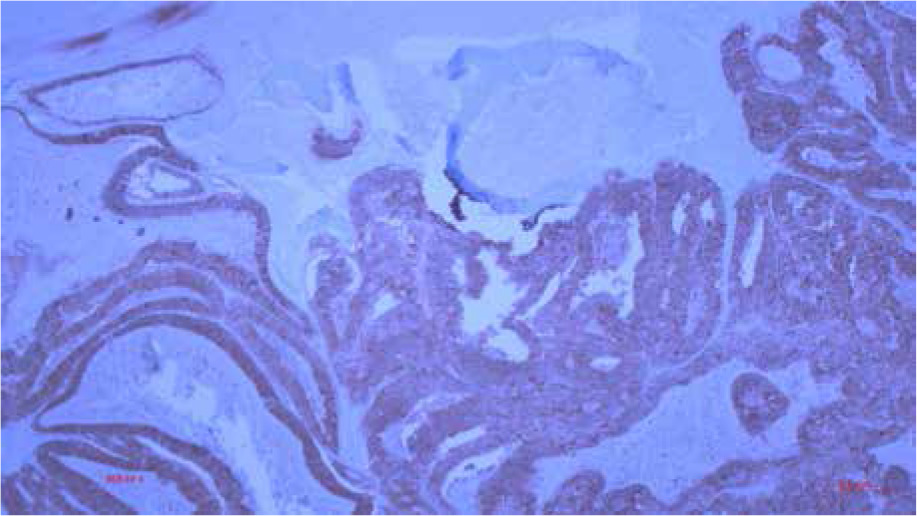

The patient recovered well from the operation, and 2 weeks after the anterior rectal resection the femoral amputation of the diseased leg was performed. Pathological examination, including the immunohistochemical profile of the tumour cells of the leg confirmed the diagnosis of metastatic colorectal carcinoma. Microscopically, tumour tissue was composed of atypical adenoid structures with foci of comedo-type necrosis. At the marginal parts of the tumour the bone beds were preserved (Figure 6). Tumour cells showed a positive immunohistochemical reaction to CK8, CK20, BER EP4, and CDX2 (Figures 7–10) and a negative reaction to CK7 (Figure 11, Table I).

Figure 7

Histological finding of metastatic CRC in the tibia with positive immunohistochemical reaction to CK8 (100×)

Figure 8

Histological finding of metastatic CRC in the tibia with positive immunohistochemical reaction to CK 20 (100×)

Figure 9

Histological finding of metastatic CRC in the tibia with positive immunohistochemical reaction to BER EP 4 (100×)

Figure 10

Histological finding of metastatic CRC in the tibia with positive immunohistochemical reaction to CDX2 (100×)